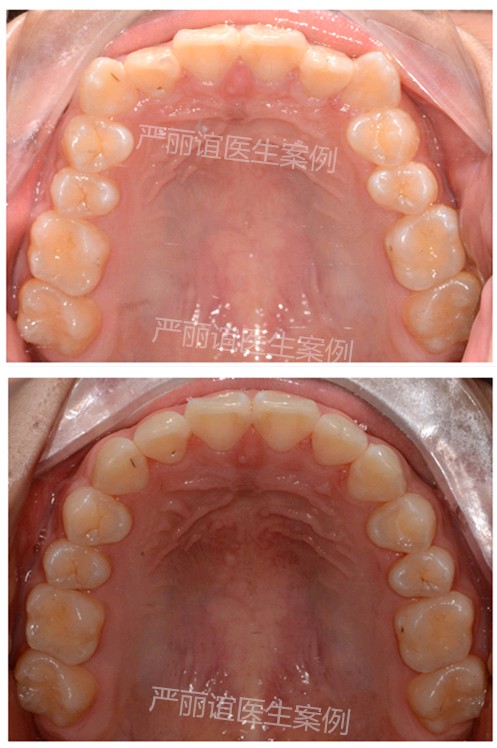

这个患者上颌两个小虎牙外凸,下颌一个畸形过大牙,自觉很影响颜值,想通过矫正改善。

检查发现她上颌最后还有一定的骨量,加上两个小虎牙外凸不是特别严重,需要2-3mm就可以排齐。下颌的畸形过大牙外面的保护层比其他牙齿厚,沟通后选择了上颌推磨牙远移,下颌片切的矫治方案。

一年半时间,矫正结束前后对比图如下。